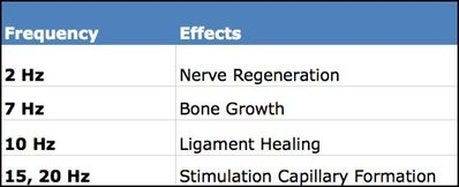

- Khi chúng ta có những suy nghĩ, cảm xúc tiêu cực thì năng lượng rung động của chúng ta sẽ thấp, khi đó chúng ta sẽ có cảm giác chán nản, nặng nề, thu lại, cơ thể cũng theo đó mà thiếu năng lượng dẫn đến mệt mỏi, uể oải, suy giảm hệ thống miễn dịch, không có năng lượng để cơ thể tự phục hồi, tự chữa lành cũng như phát triển toàn diện về thể chất và não bộ. Và đen đủi hơn là lúc này, luật hấp dẫn bắt đầu hoạt động. Nó lại tiếp túc hấp dẫn những năng lượng tiêu cực đến và bám vào chúng ta. “Chó cắn áo rách”, đã đen lại còn lắm lông :)) Và khi đó ta rất muốn đc chia sẻ với mọi người, nhất là với những người tích cực để có thể hấp thu được năng lượng của họ, hoặc đi đền, chùa, những nơi có năng lượng tích cực, hoặc 1 biện pháp tâm lí nào đó.

- Tần số rung động cao sẽ xu hướng giãn nở, toả ra, chúng ta sẽ luôn thấy nhẹ nhàng, thanh thản, muốn cho đi và yêu thương vô điều kiện. Cơ thể cảm giác khoẻ mạnh, tràn trề sinh lực, hệ miễn dịch tăng cường, đẩy mạnh sự phát triển của cơ thể, khả năng tự hồi phục và chữa lành. Luật hấp dẫn cũng sẽ hoạt động ở đây và hấp dẫn những điều tuyệt vời đến với ta.

Nếu cơ chế tự chữa lành hoạt động tốt và miễn dịch khoẻ mạnh thì nó mạnh hơn tất cả các loại thuốc hay kháng sinh trên đời này cộng lại. Cô vít cô veo gì cũng chấp tất!

– Âm nhạc hoặc các âm thanh tự nhiên, âm thanh của các nhạc cụ cơ học. Các bạn có thể chọn nghe các bản nhạc ở các tần số tương ứng

Còn mình hay dùng các loại nhạc cụ chữa lành, sound therapy để tăng tần số rung động cơ thể